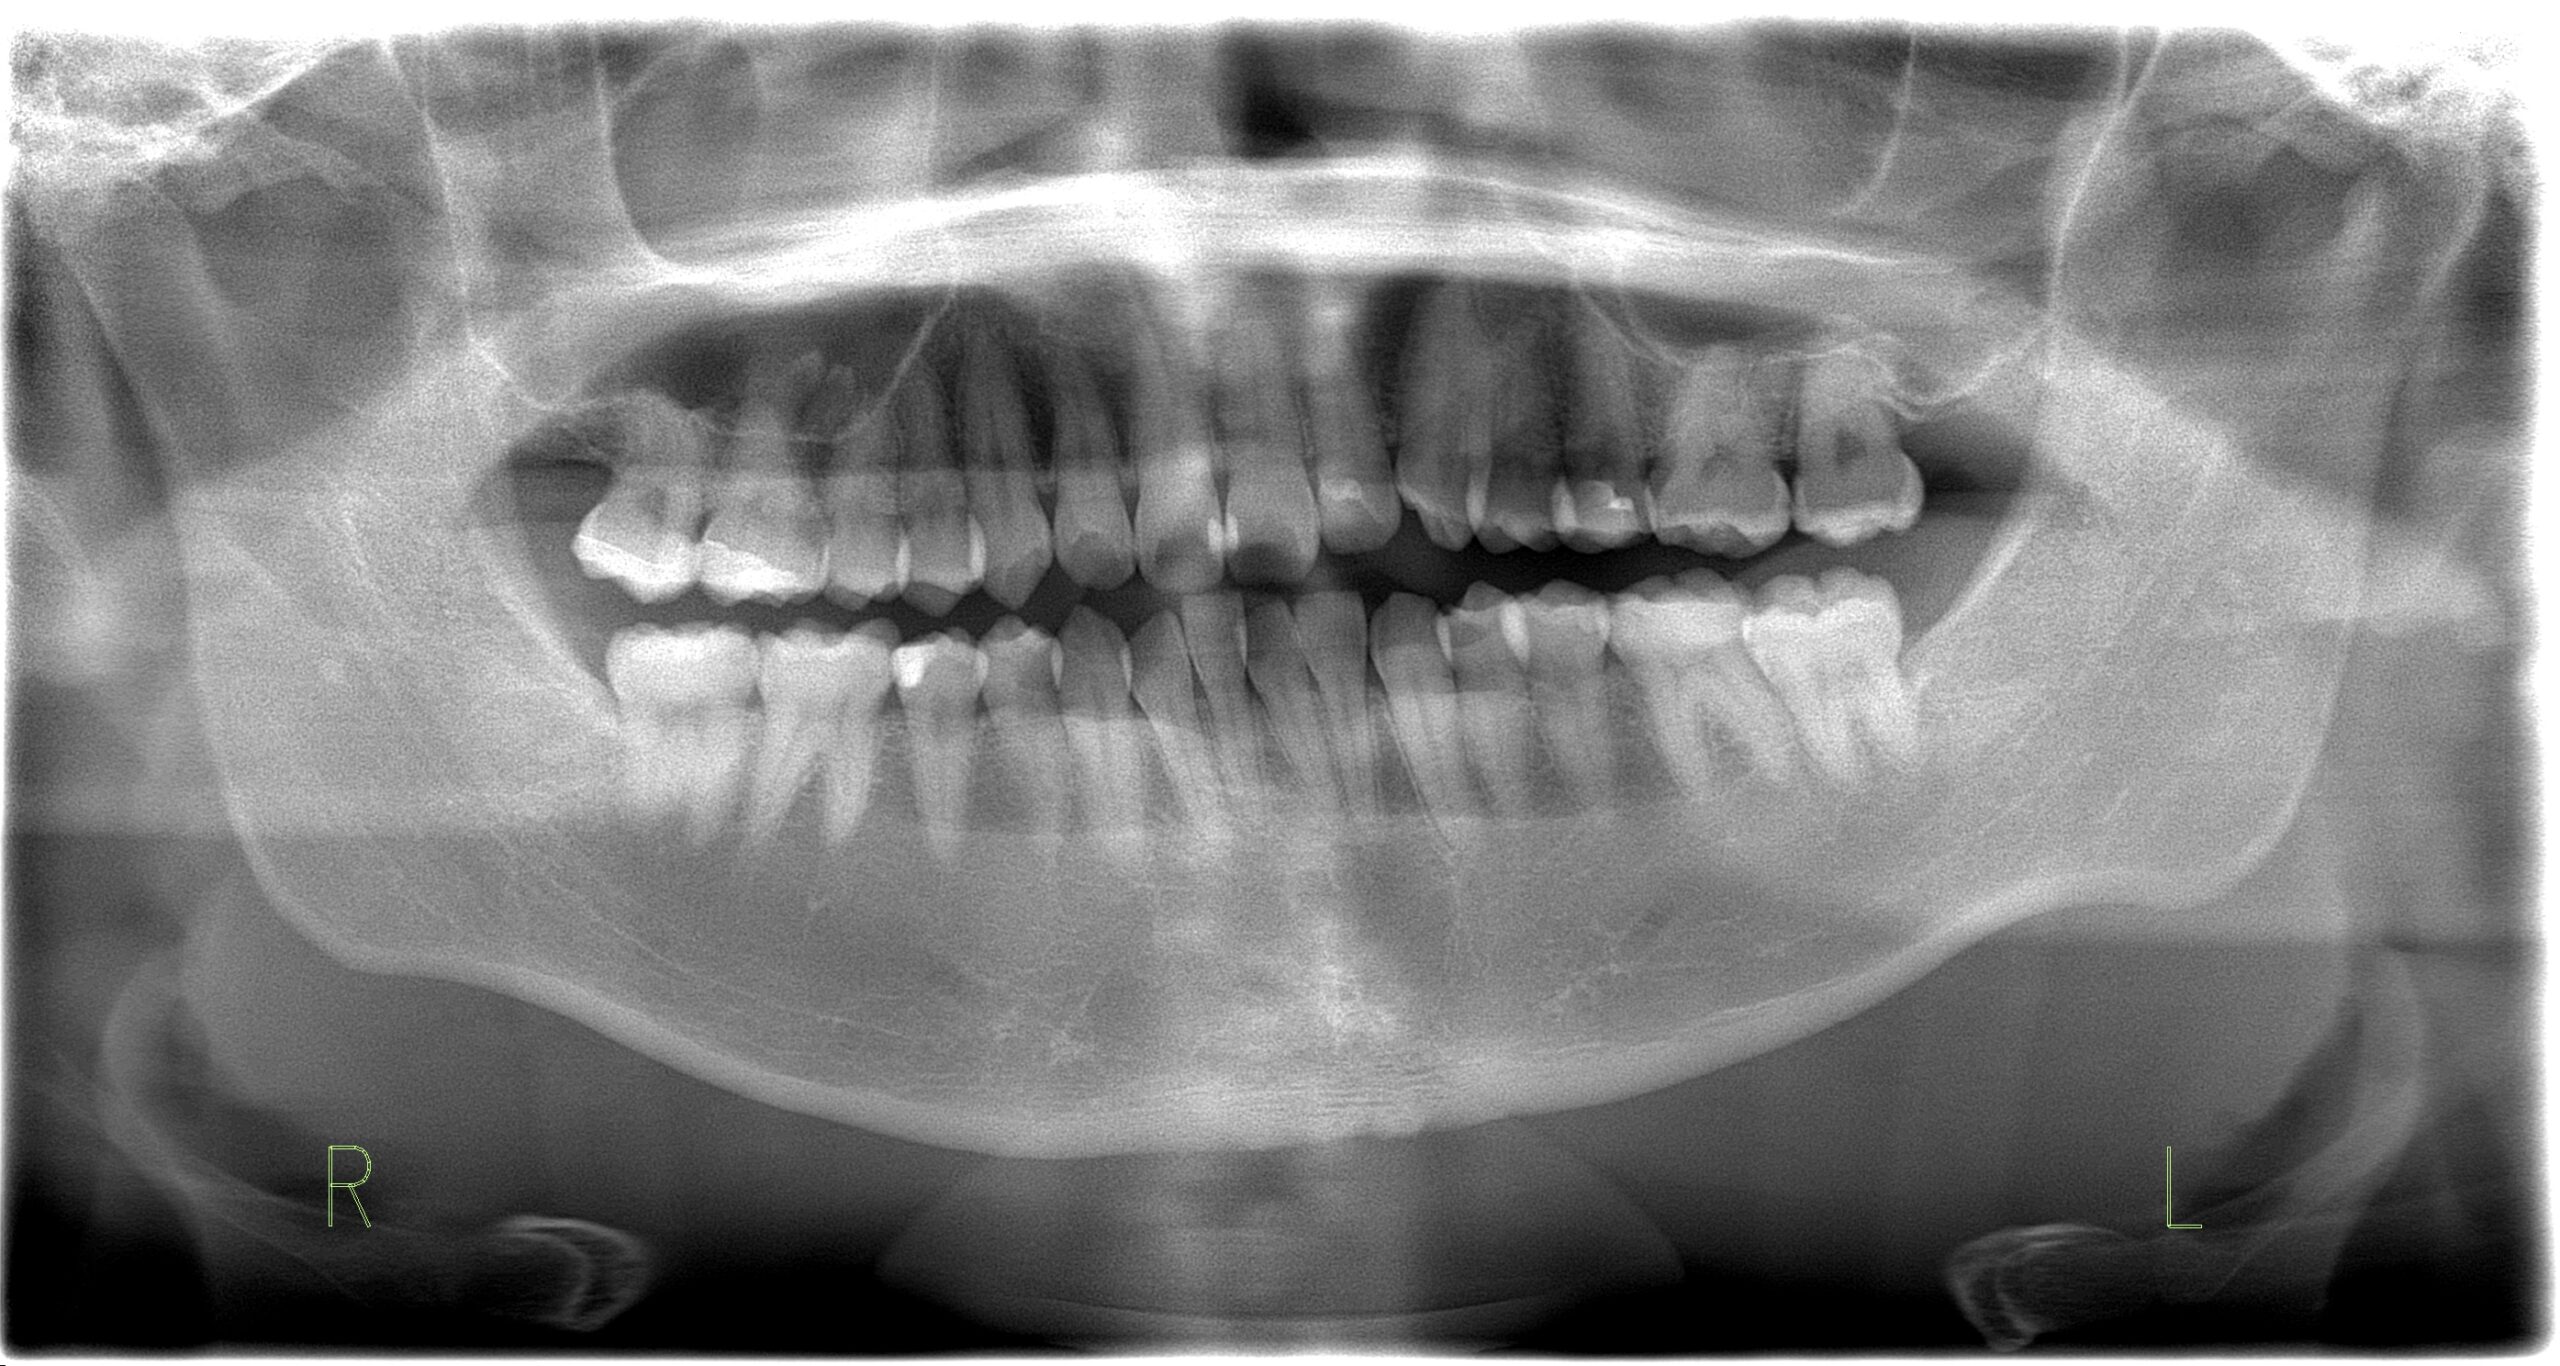

親知らず抜歯

親知らずの抜歯 32歳女性

Before

-

After

主訴 悪いところがないかをみて欲しい 診断名 親知らずの周囲炎 年齢・性別 32歳・女性 治療期間・回数 1ヶ月・3回 費用 保険診療 デメリット・注意点 数日間痛み、腫れがでます。 抜歯当日は激しい運動等血のめぐりが良くなることはさけてください。 下顎の親知らず抜歯後は唇、舌にしびれがでることがあります。 -